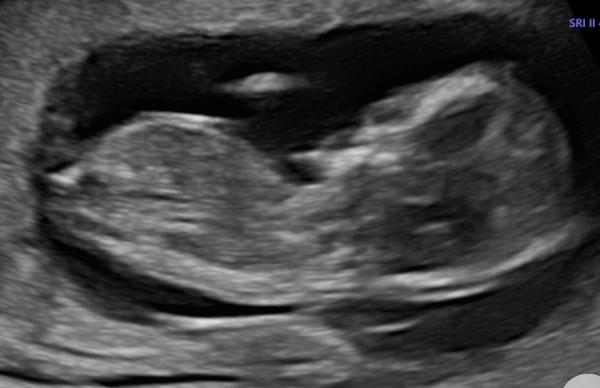

Huhu, wer mag kann ja gern mal schauen ob man schon erkennen kann welches Geschlecht es wird. Es gibt da ja verschiedene Theorien. BIn einfach zu ungeduldig und gespannt:)